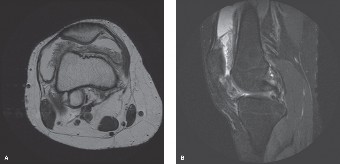

Computed Tomography and Templating

A high-resolution, multi-detector Computed Tomography scan of the pelvis and lumbosacral spine was subsequently performed to better delineate the bony architecture, tumor extent, and matrix characteristics. The CT revealed a destructive, lytic lesion involving S2 to S4, with significant anterior cortical breach and an extensive anterior sacral soft tissue component. Areas of internal septation and a hypodense mucoid matrix were noted. There was no evidence of overt chondroid or osteoid matrix calcification.

The CT scan provided crucial information regarding the extent of bony involvement, potential for pathological fracture, and proximity to critical structures such as the mesorectal fascia, rectum, and major pelvic vessels (internal iliac artery and vein branches). Based on the CT images, 3D templating was initiated to map the precise osteotomy planes required for an en bloc resection.

Magnetic Resonance Imaging

To fully characterize the soft tissue extent, epidural involvement, and neural element compromise, a contrast-enhanced Magnetic Resonance Imaging study of the lumbosacral spine and pelvis was obtained. MRI is the gold standard for evaluating sacral tumors.

The MRI demonstrated a large, lobulated mass centered in the lower sacrum. On T1-weighted images, the lesion was isointense to hypointense relative to skeletal muscle. On T2-weighted and STIR sequences, the tumor exhibited striking hyperintensity, characteristic of the high water content found in the myxoid and mucinous matrix of a chordoma. The classic "thumbprint sign" or lobular architecture with low-signal internal septations was clearly visible. Following gadolinium administration, the lesion demonstrated heterogeneous enhancement.

Crucially, the MRI detailed the tumor's relationship with the sacral nerve roots. The S1 roots were displaced superiorly but appeared uninvolved by gross tumor. The S2 roots were encased bilaterally, and the S3-S5 roots were completely obliterated by the mass. The tumor extended anteriorly, pushing against the presacral fascia, but a distinct fat plane was maintained between the tumor capsule and the posterior wall of the rectum, suggesting that a clear anterior margin could be achieved without necessitating a bowel resection.